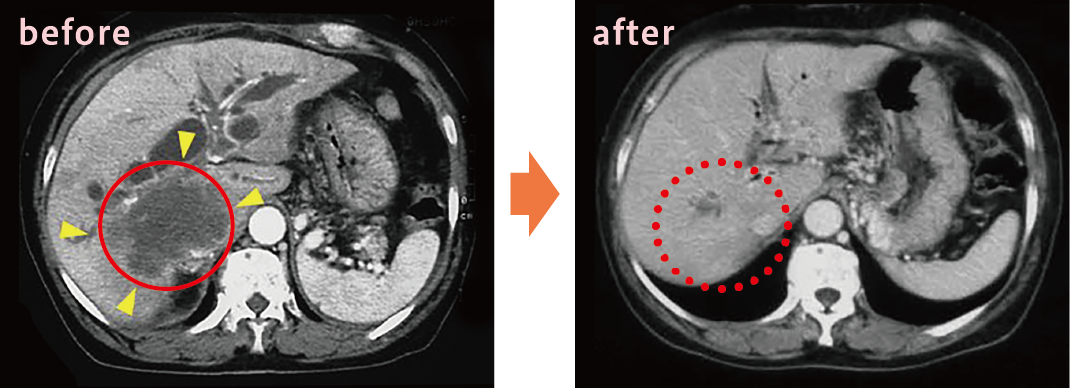

胆管細胞癌・多発性肝転移の症例

65歳の患者さんの治療例。赤い丸で示した部分、治療前(before)は黒い影のように見えているがんが、薬物治療後(after)はほとんど消失していることがわかる。